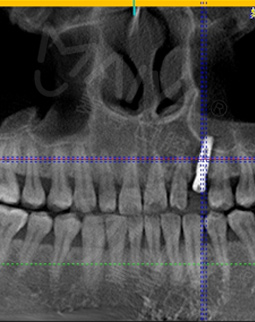

关于我牙齿的问题,多多少少我也了解,缺牙后有烤瓷牙、活动假牙和种植牙怎么选?来到这里,医生用专业的CT给我检查牙齿后,指出我的牙齿情况时为残根,邻侧间隙较大,牙龈正常,咬合空间尚可,可用骨高度尚可,医生综合给我分析了烤瓷牙、活动假牙、种植牙的优缺点,立马决定在麦芽种植牙!

兜兜转转,最终还是选择了这里种牙!是的,我去了其他家机构,多方对比,对比种植牙多少钱,对比医院资质、各种设备等等,我还是觉得这里是我的不二之选!上次过来时候医生定制了微创即刻种植的修复方案,即是即拔即种,能快速恢复牙齿的咀嚼功能,极大节省治疗时间。这次在身体条件完全符合种牙的情况下,和医生护士一起走入手术室,手术室是三通道的,很干净~另外必须说一下真的是硕博专家种牙的,为我种牙的是西安交大双博士专家,当然其他的种牙医生肯定也很厉害!